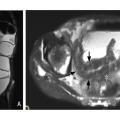

Témoins d’inflammation : œdème pariétal et lésions muqueuses

En pratique, les éléments les plus utiles pour l’évaluation de l’inflammation sont la recherche d’un hyper­signal T2, témoin d’un œdème de la paroi, et la recherche de lésions muqueuses, en par­ticulier d’ulcères ou de micro-abcès pariétaux (fig. 3).7

Comme à l’échographie, une hyperhémie ou un épaississement de la paroi au-delà de 4 mm sont considérés comme des signes d’inflammation pathologiques.7 Enfin, les séquences de diffusion facilitent le repérage des segments inflammatoires apparaissant en restriction de diffusion.